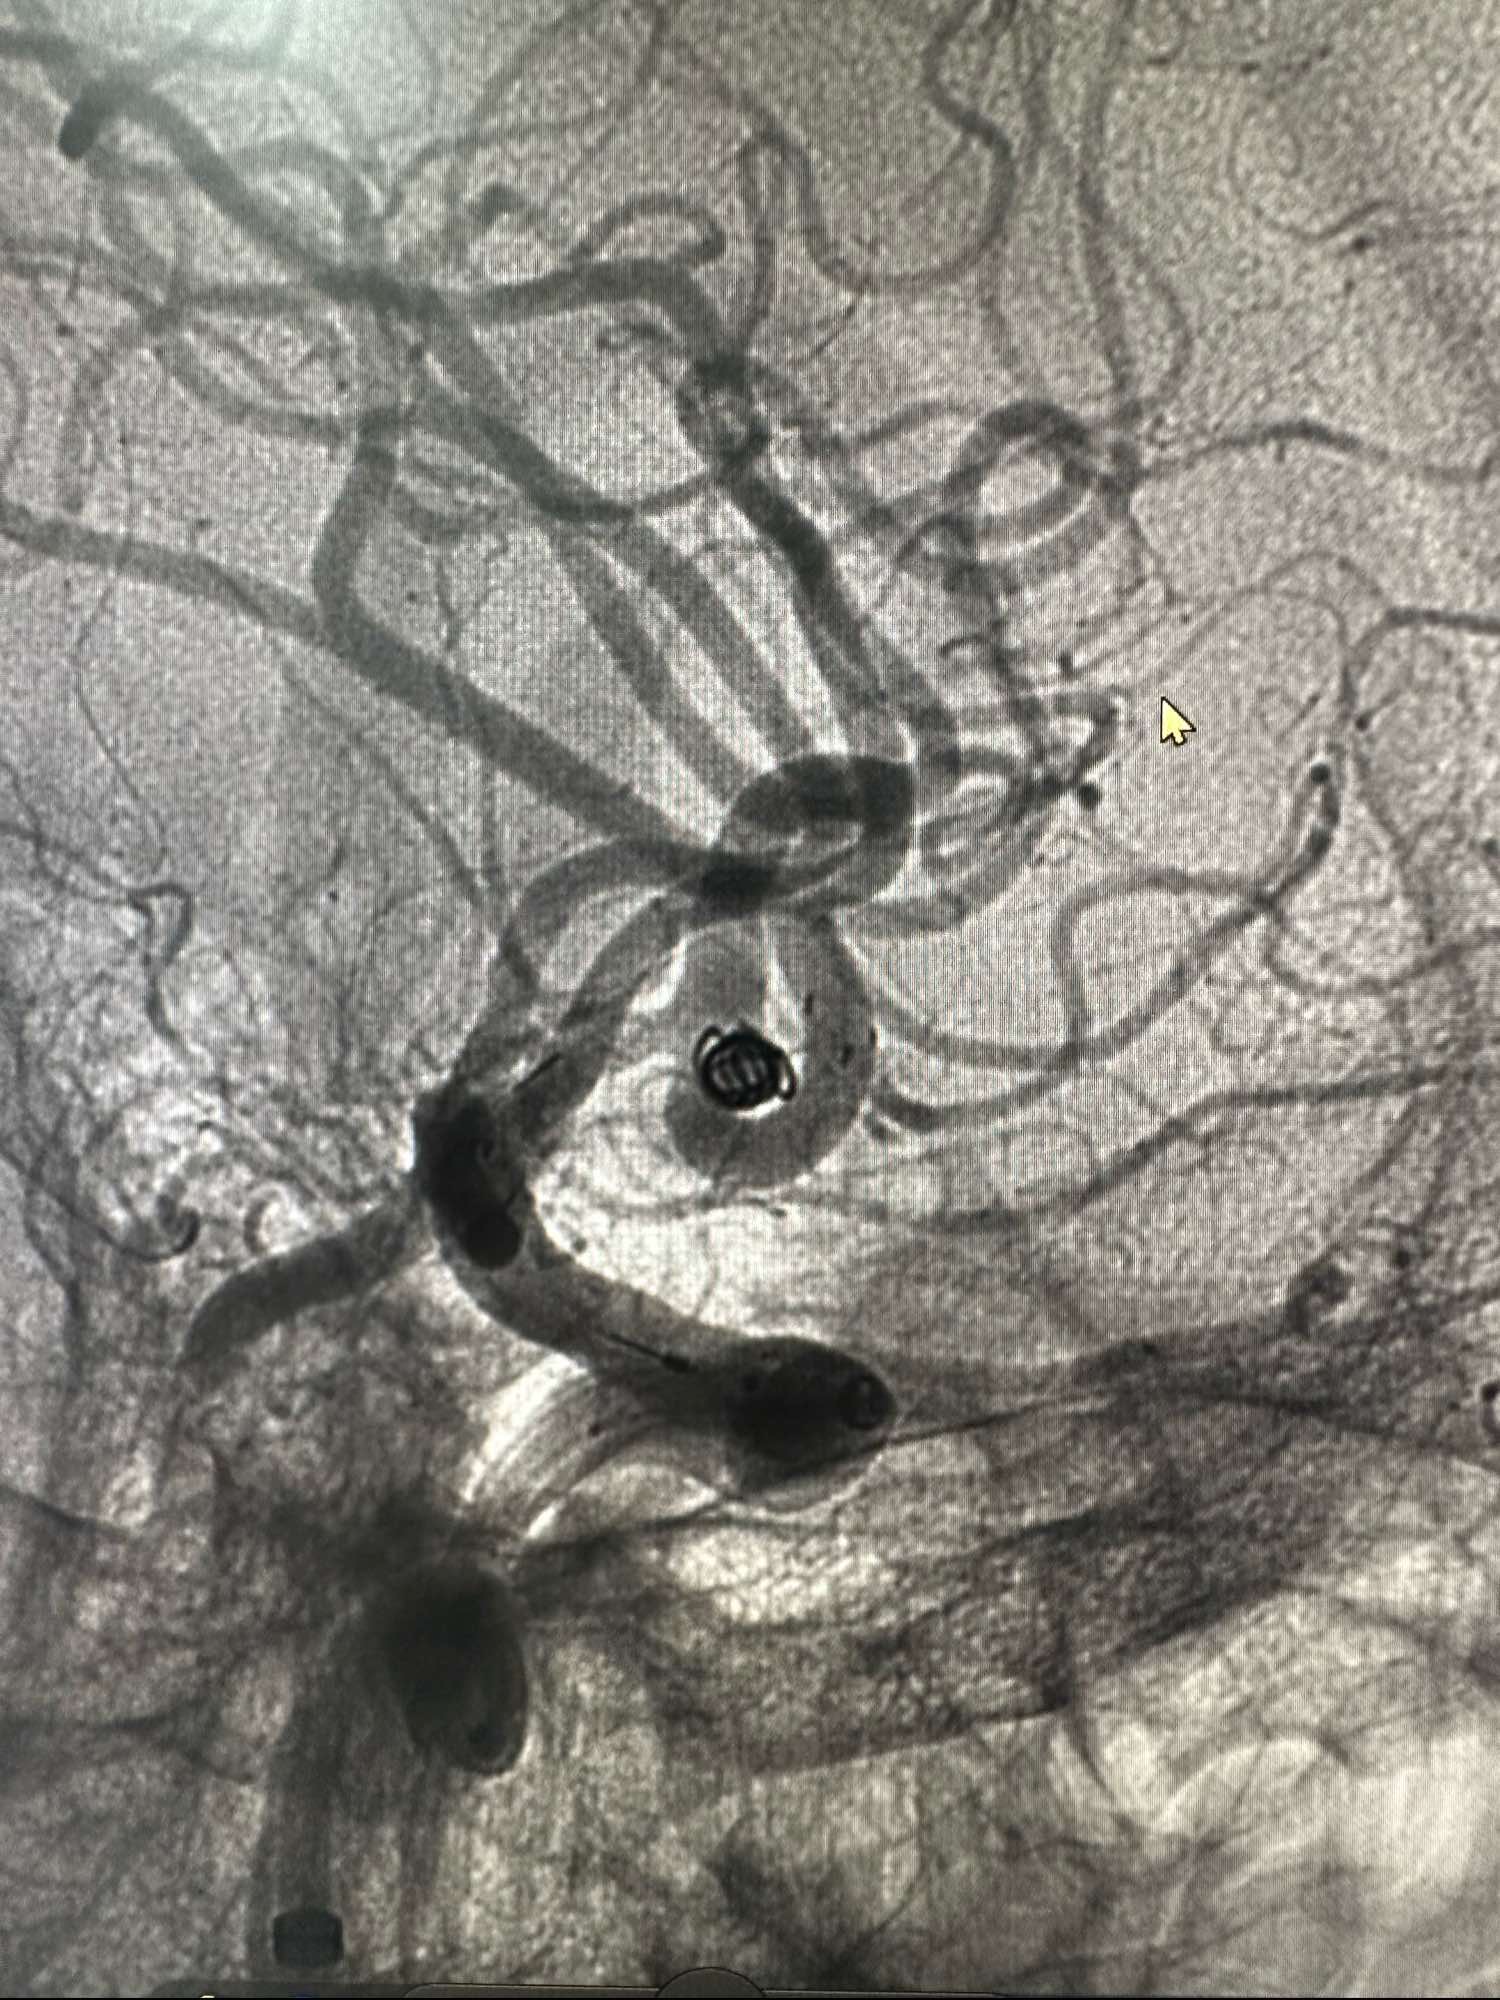

第一枚圈选择3*8的加奇的3D,出了几个襻后直接释放Atlas支架3*21

第一枚圈填塞后的形态,圈没有影响上干血流

第一枚圈的形态

后续再次填入2*4的加奇圈,另外一个角度造影见动脉瘤已经不显影